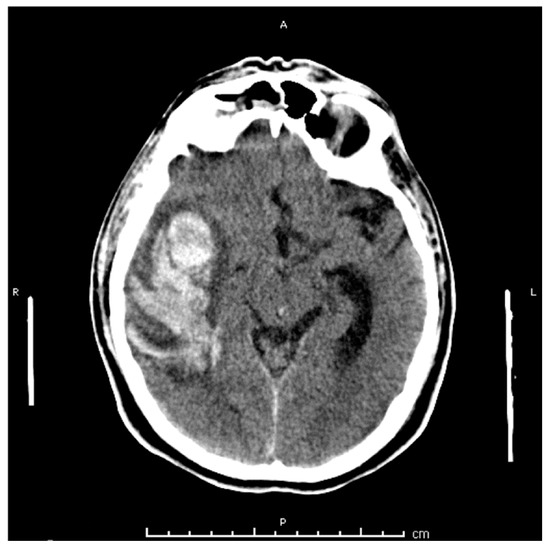

2. Case Presentation